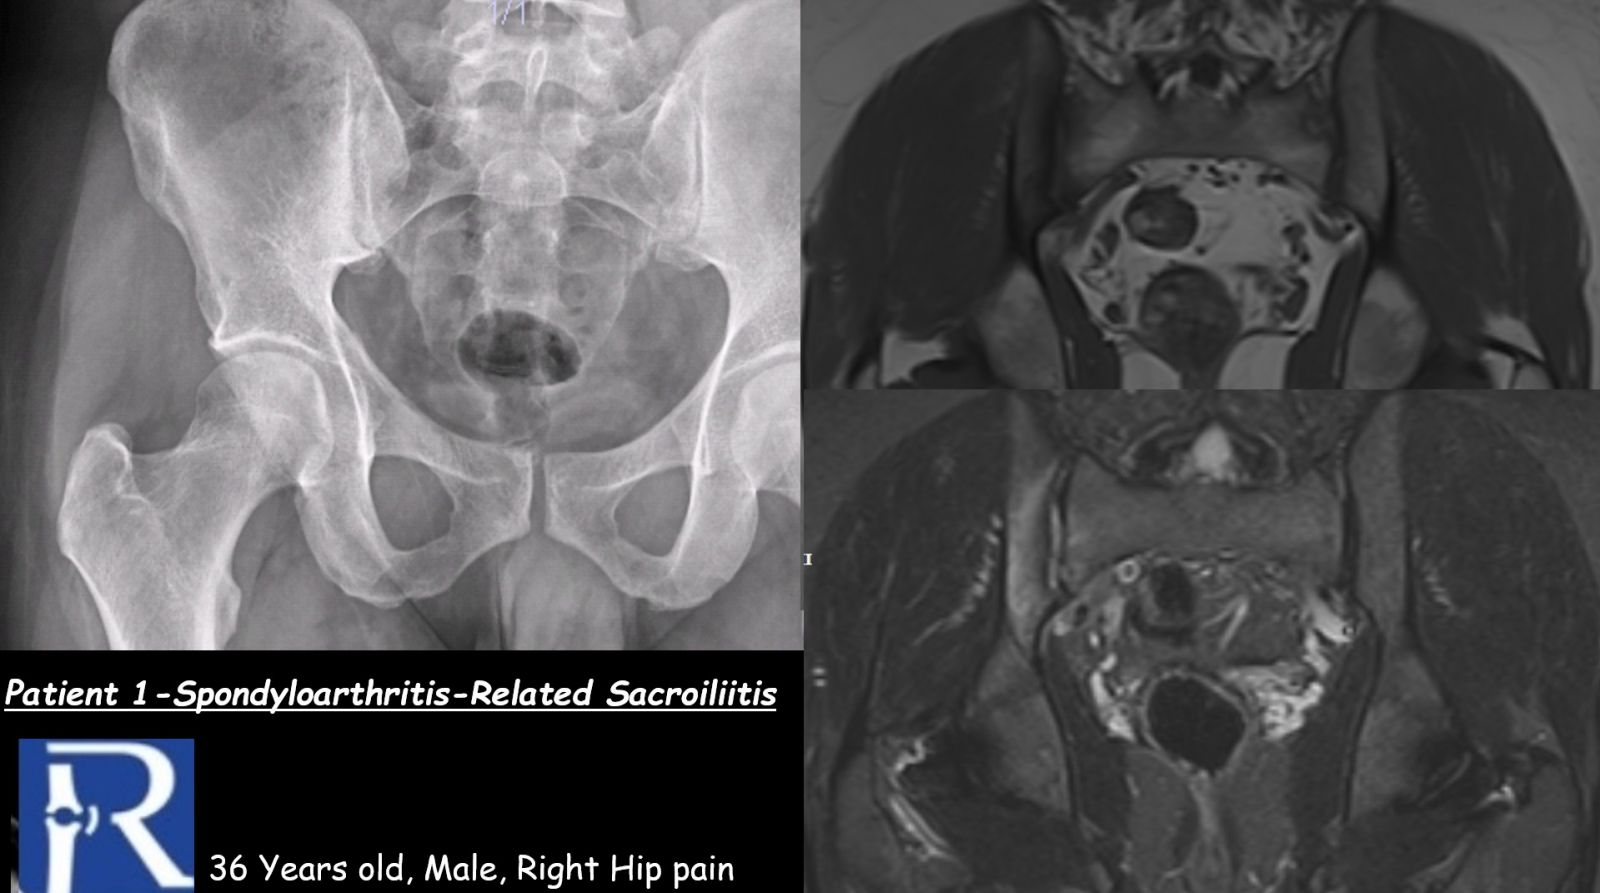

Case 1

Clinical presentation:

A 36-year-old man presenting with right hip pain. The patient is HLA-B27 positive.

MRI findings:

MRI demonstrates bone marrow edema–like signal changes involving the right sacroiliac joint, with predominant involvement of the iliac side. The imaging appearance is consistent with spondyloarthritis-associated sacroiliitis.

It should be noted that these findings are based on images acquired as part of a hip MRI examination; therefore, the images do not represent a dedicated, optimized sacroiliac joint MRI protocol.

Radiography:

Conventional radiographs demonstrate grade II sacroiliitis.